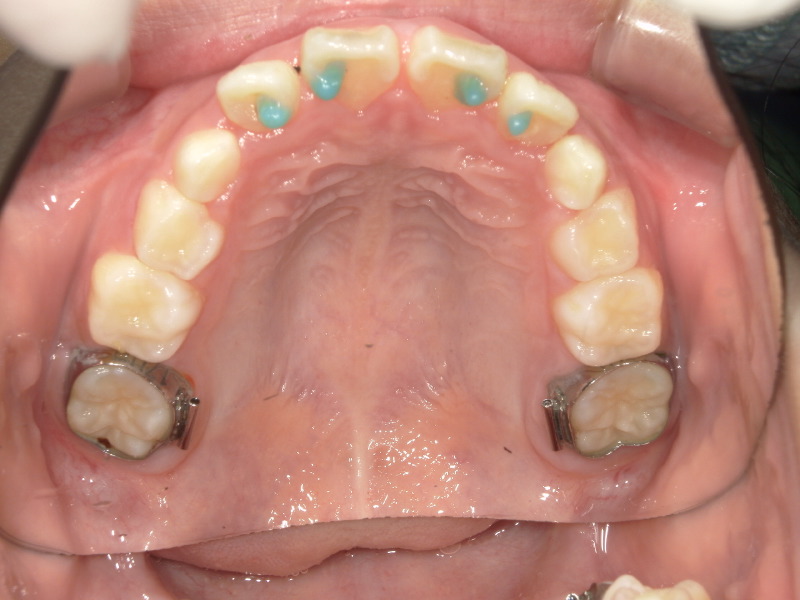

スタートから一年後の歯並びです。

初めは平坦気味だった2番目の歯もアーチに沿って綺麗になっています。

ですがまだ生え変わりがあることと、スペースに余裕はないため装置を装着しました。

歯と歯にしっかりと隙間ができて広がっています。

装置をつけると一時的に出っ歯っぽく見えていますがここからまた上顎は変わっていきます。